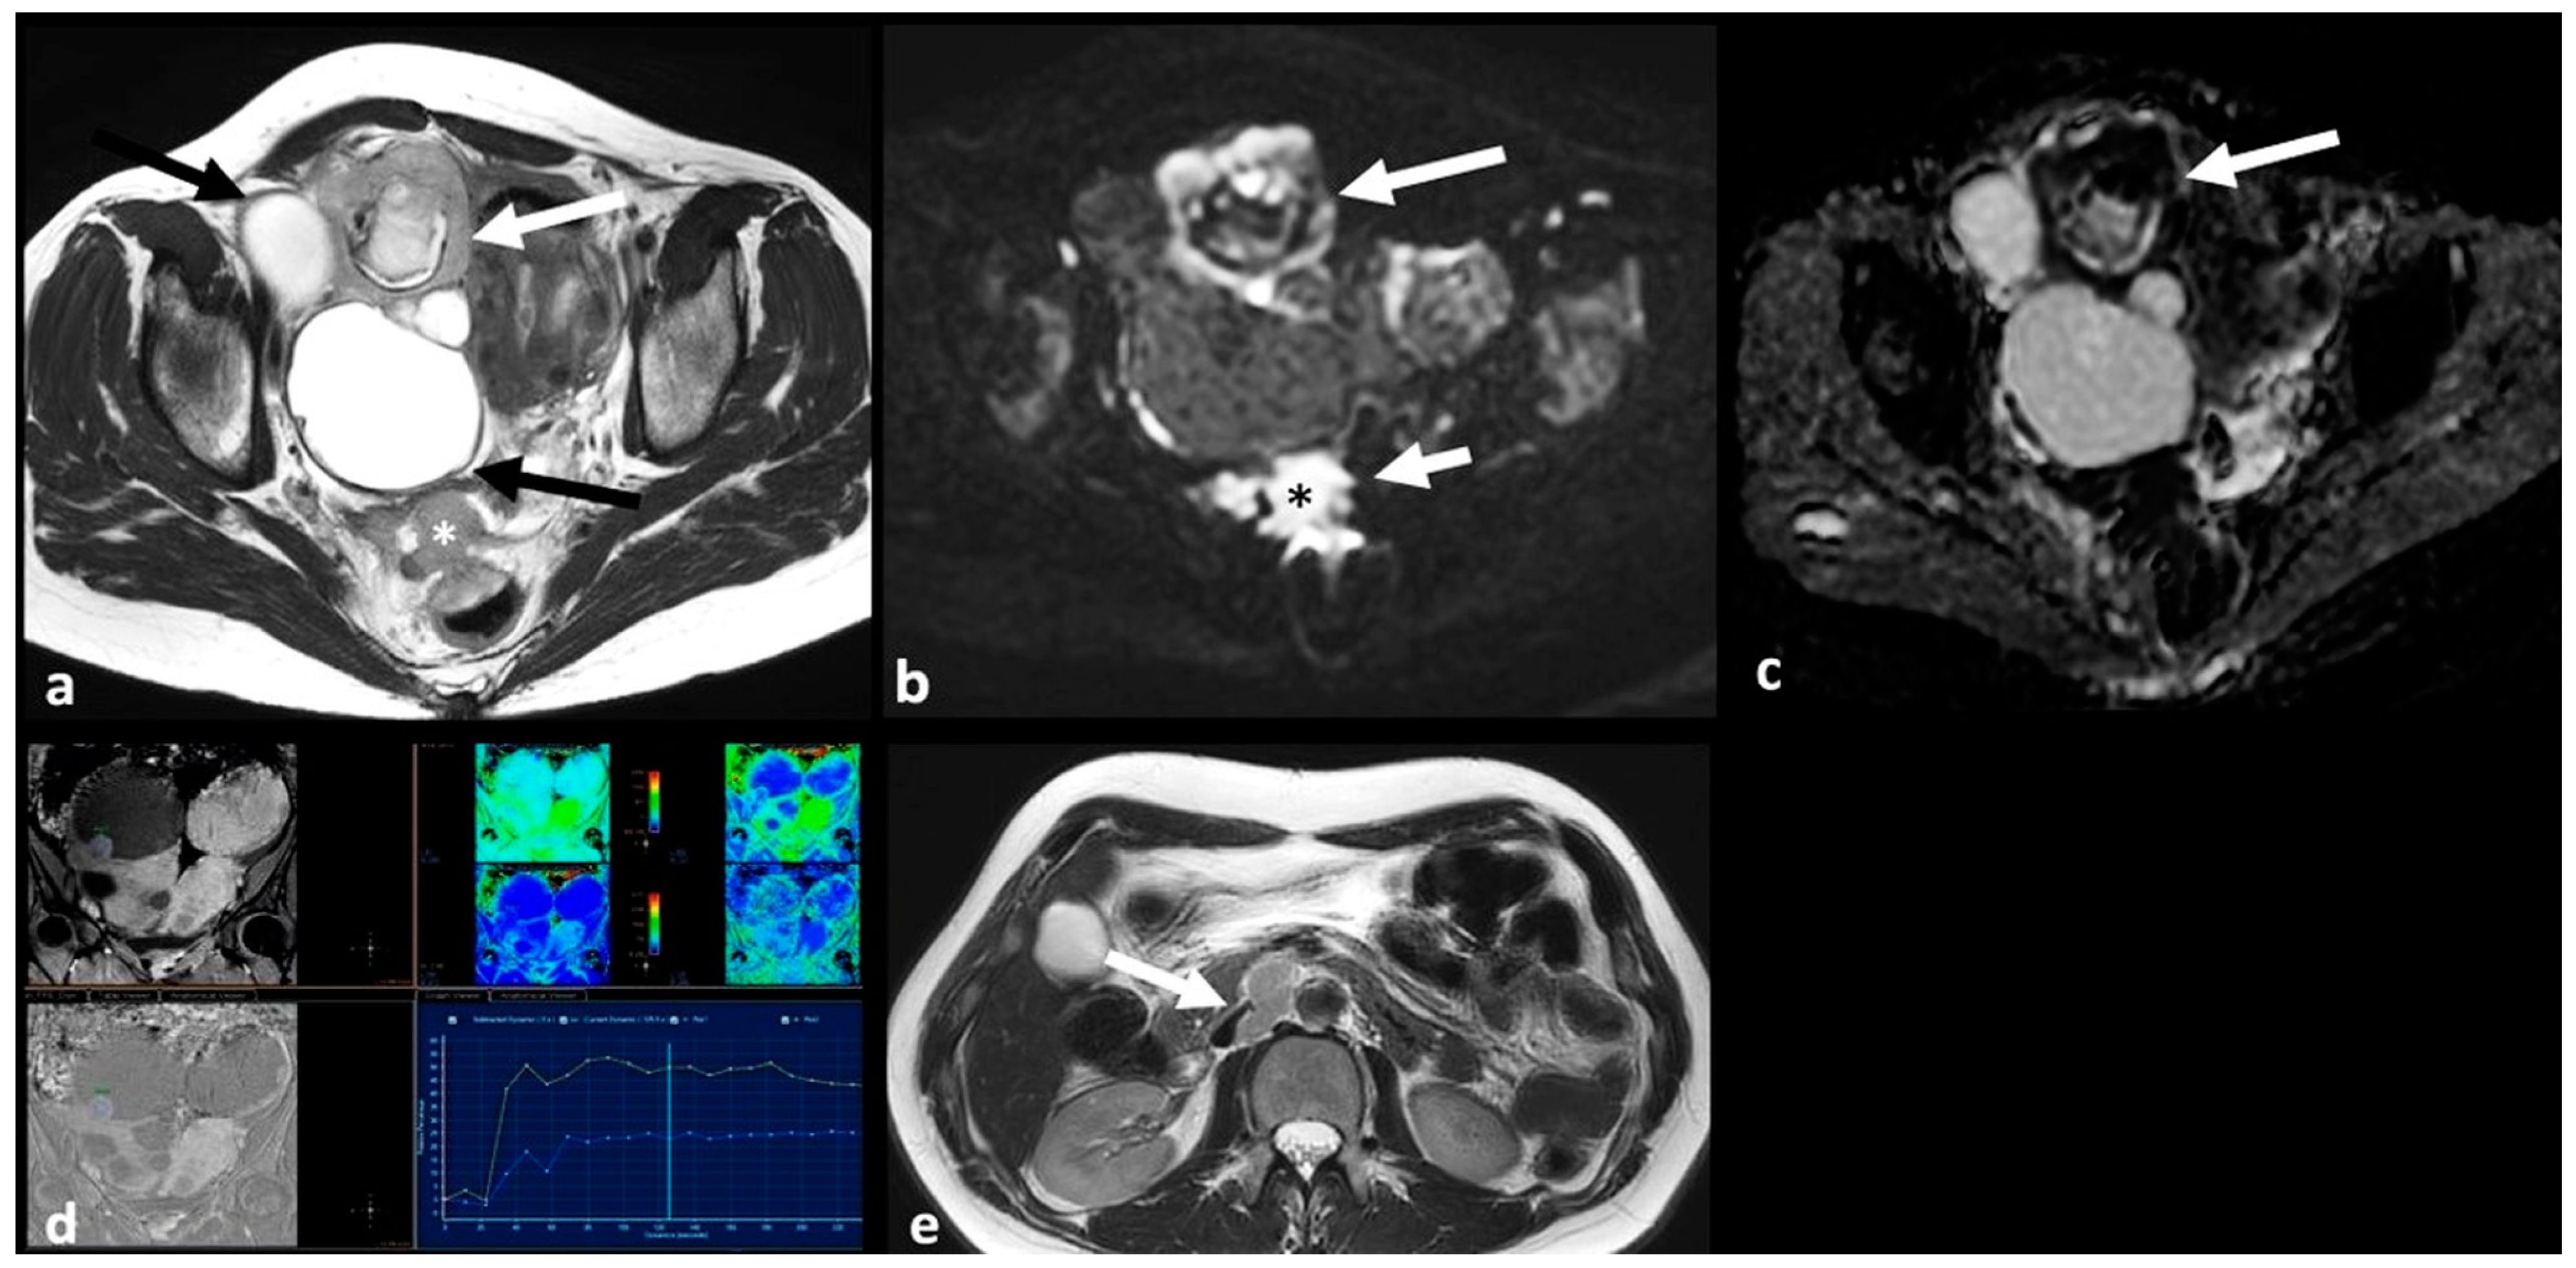

2.1.1. High-Grade Serous Cystadenocarcinoma (HGSC)

2.2.1. Cystadenofibroma

2.2.2. Fibrothecoma

2.2.3. Pelvic Inflammatory Disease—Tubo-Ovarian Abscess (TOA)

2.3.3. Granulosa Cell Tumor

2.3.4. Lymphoma